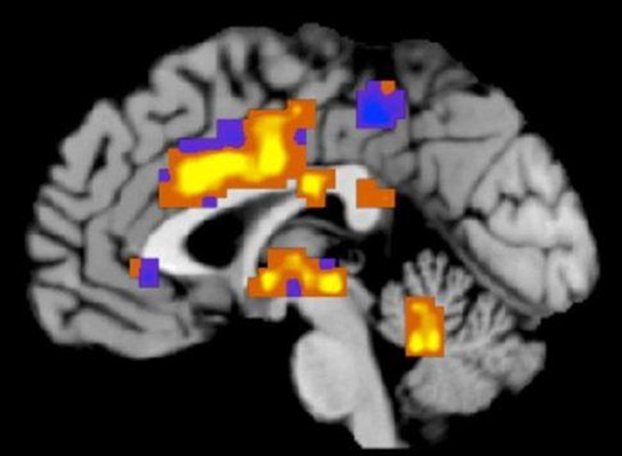

Η μελέτη αποκάλυψε ένα χαρακτηριστικό μοτίβο εγκεφαλικής δραστηριότητας το οποίο εμφανίζεται όταν κάποιος εκτίθεται σε οδυνηρή ζέστη, αλλά όχι στην απλή θερμότητα. Η ισχύς αυτής της «νευρωνικής υπογραφής» του πόνου ήταν πιο έντονη όταν το ερέθισμα γινόταν πιο επώδυνο, ενώ αντίθετα εξασθενούσε όταν οι εθελοντές είχαν πάρει παυσίπονα.

Η μελέτη, η οποία πραγματοποιήθηκε από ερευνητές τεσσάρων αμερικανικών πανεπιστημίων, εξέτασε 144 υγιείς, νέους εθελοντές, οι οποίοι υποβλήθηκαν σε λειτουργική μαγνητική τομογραφία (fMRI) την ώρα που μια ειδική συσκευή θερμαινόταν πάνω στο χέρι τους.

Η μέθοδος fMRI είναι μια παραλλαγή της μαγνητικής τομογραφίας που παρακολουθεί αυξομειώσεις στη ροή αίματος στον εγκέφαλο σε σχεδόν πραγματικό χρόνο. Και κάθε αύξηση της ροής σε μια συγκεκριμένη περιοχή υποδηλώνει αύξηση στη δραστηριότητα αυτής της περιοχής.

Αναλύοντας τα μοτίβα της εγκεφαλικής δραστηριότητας, οι ερευνητές ήταν σε θέση να προβλέψουν αν ο εθελοντής πονούσε και πόσο στο 93% των περιπτώσεων.

Όπως επισημαίνει ο ίδιος, το μυστικό της επιτυχίας στη νέα μελέτη δεν αποκλείεται να είναι το γεγονός ότι οι τομογραφίες εξέτασαν ταυτόχρονα αρκετές διαφορετικές περιοχές του εγκεφάλου, σε αντίθεση με προηγούμενες έρευνες, οι οποίες αναζητούσαν τον πόνο σε συγκεκριμένα σημεία.